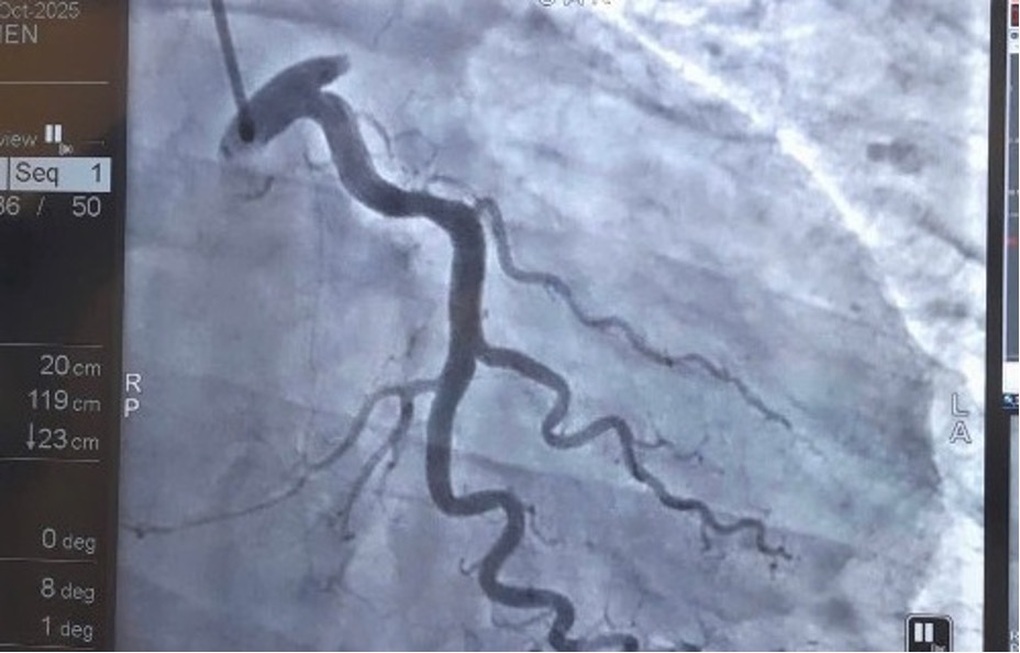

Hình ảnh hình chụp động mạch vành trái (Left Coronary Artery ) cho thấy tắc hoàn toàn ngay từ lỗ vào của động mạch liên thất trước (LAD) - một vị trí rất nguy hiểm (Ảnh: BVCC).

Các bác sĩ đã tiến hành hút huyết khối, loại bỏ một lượng lớn cục máu đông gây bít tắc hoàn toàn lòng mạch. Sau đó, đặt một stent phủ thuốc kích thước 4.0 x 48 mm vào vị trí tổn thương để tái thông hoàn toàn dòng máu nuôi cơ tim. Toàn bộ quá trình kéo dài khoảng 80 phút, được thực hiện liên tục, chính xác và an toàn.